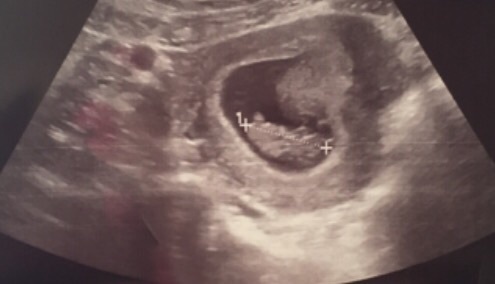

I'd love twins, but only one in there at early scan for 9+1 last week and I think it looks like a boy 😂 not sure what I'm basing this on!

parney love the pic

I had a private reassurance scan last week too because I'm so anxious this pregnancy at 8wks+. One lovely strong heartbeat. DH was hoping for a surprise 2 (he wants 3kids) . I don't think we'll be finding out the gender this time round. We already have DD1 and I'm quite indifferent btw boy/girl. It'll be a surprise regardless I think and will keep grandparents guessing for longer Grin